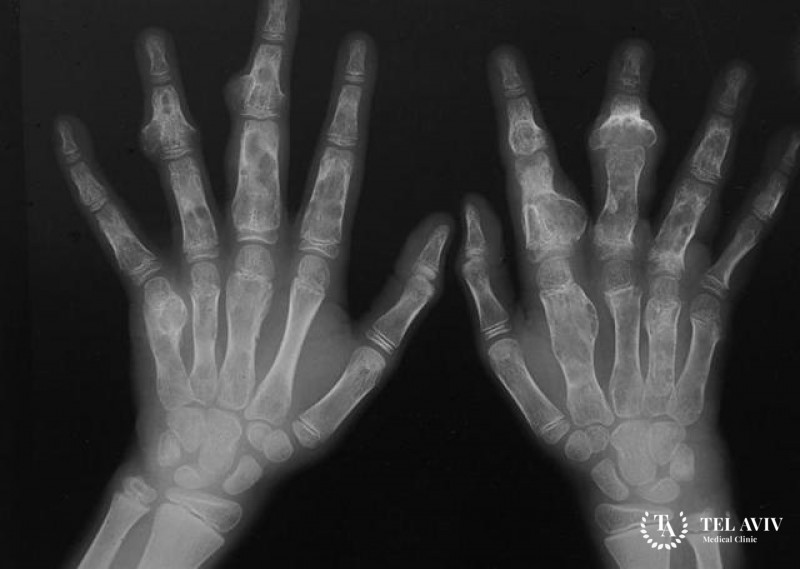

Хондрома может быть обнаружена совершенно случайно. Но для постановки диагноза специалисту требуется видеть полную клиническую картину. Чтобы ее получить, нужно собрать анамнестическую информацию, провести осмотр и дополнительные обследования, которые могут включать в себя:

- рентгенографию;